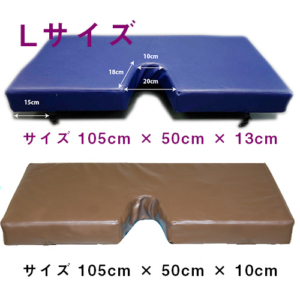

迷いなく、即座に Advanced Image

診断スピードに直結する「高画質」。

不安を抱える患者さんが、より早く安心できるように。

それを叶えるのは、迷うことなく自信を持って見極められるワンランク上の高画質。

上位機種に注がれた技術を随所に活かした1台です。

いつでも、どこでも Light & Compact

院内を軽やかに駆けめぐる「機動力」

スペースの限られた診療室や病棟はもちろん、必要に応じて救急や手術室など、

様々なシーンで使いこなせるよう、軽量&コンパクトな設計を追求しました。

重量 67kg

モニター 23.8inch

高さ 1345-1595mm

幅 495mm

奥行き 685mm